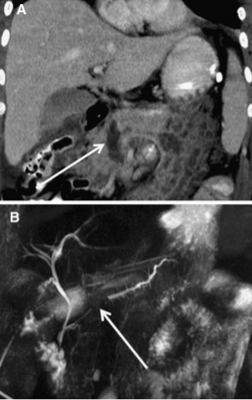

Изображение 4. 55-летний мужчина после удара бейсбольной битой по животу. На МСКТ-снимке (А) обнаружена большая рваная рана головки поджелудочной железы (стрелка), затрагивающая более 50 % толщины паренхимы и указывающая на высокую вероятность повреждения протока.

На магнитно-резонансной холангиопанкреатографии (В) у того же пациента подтверждается повреждение протока (стрелка).